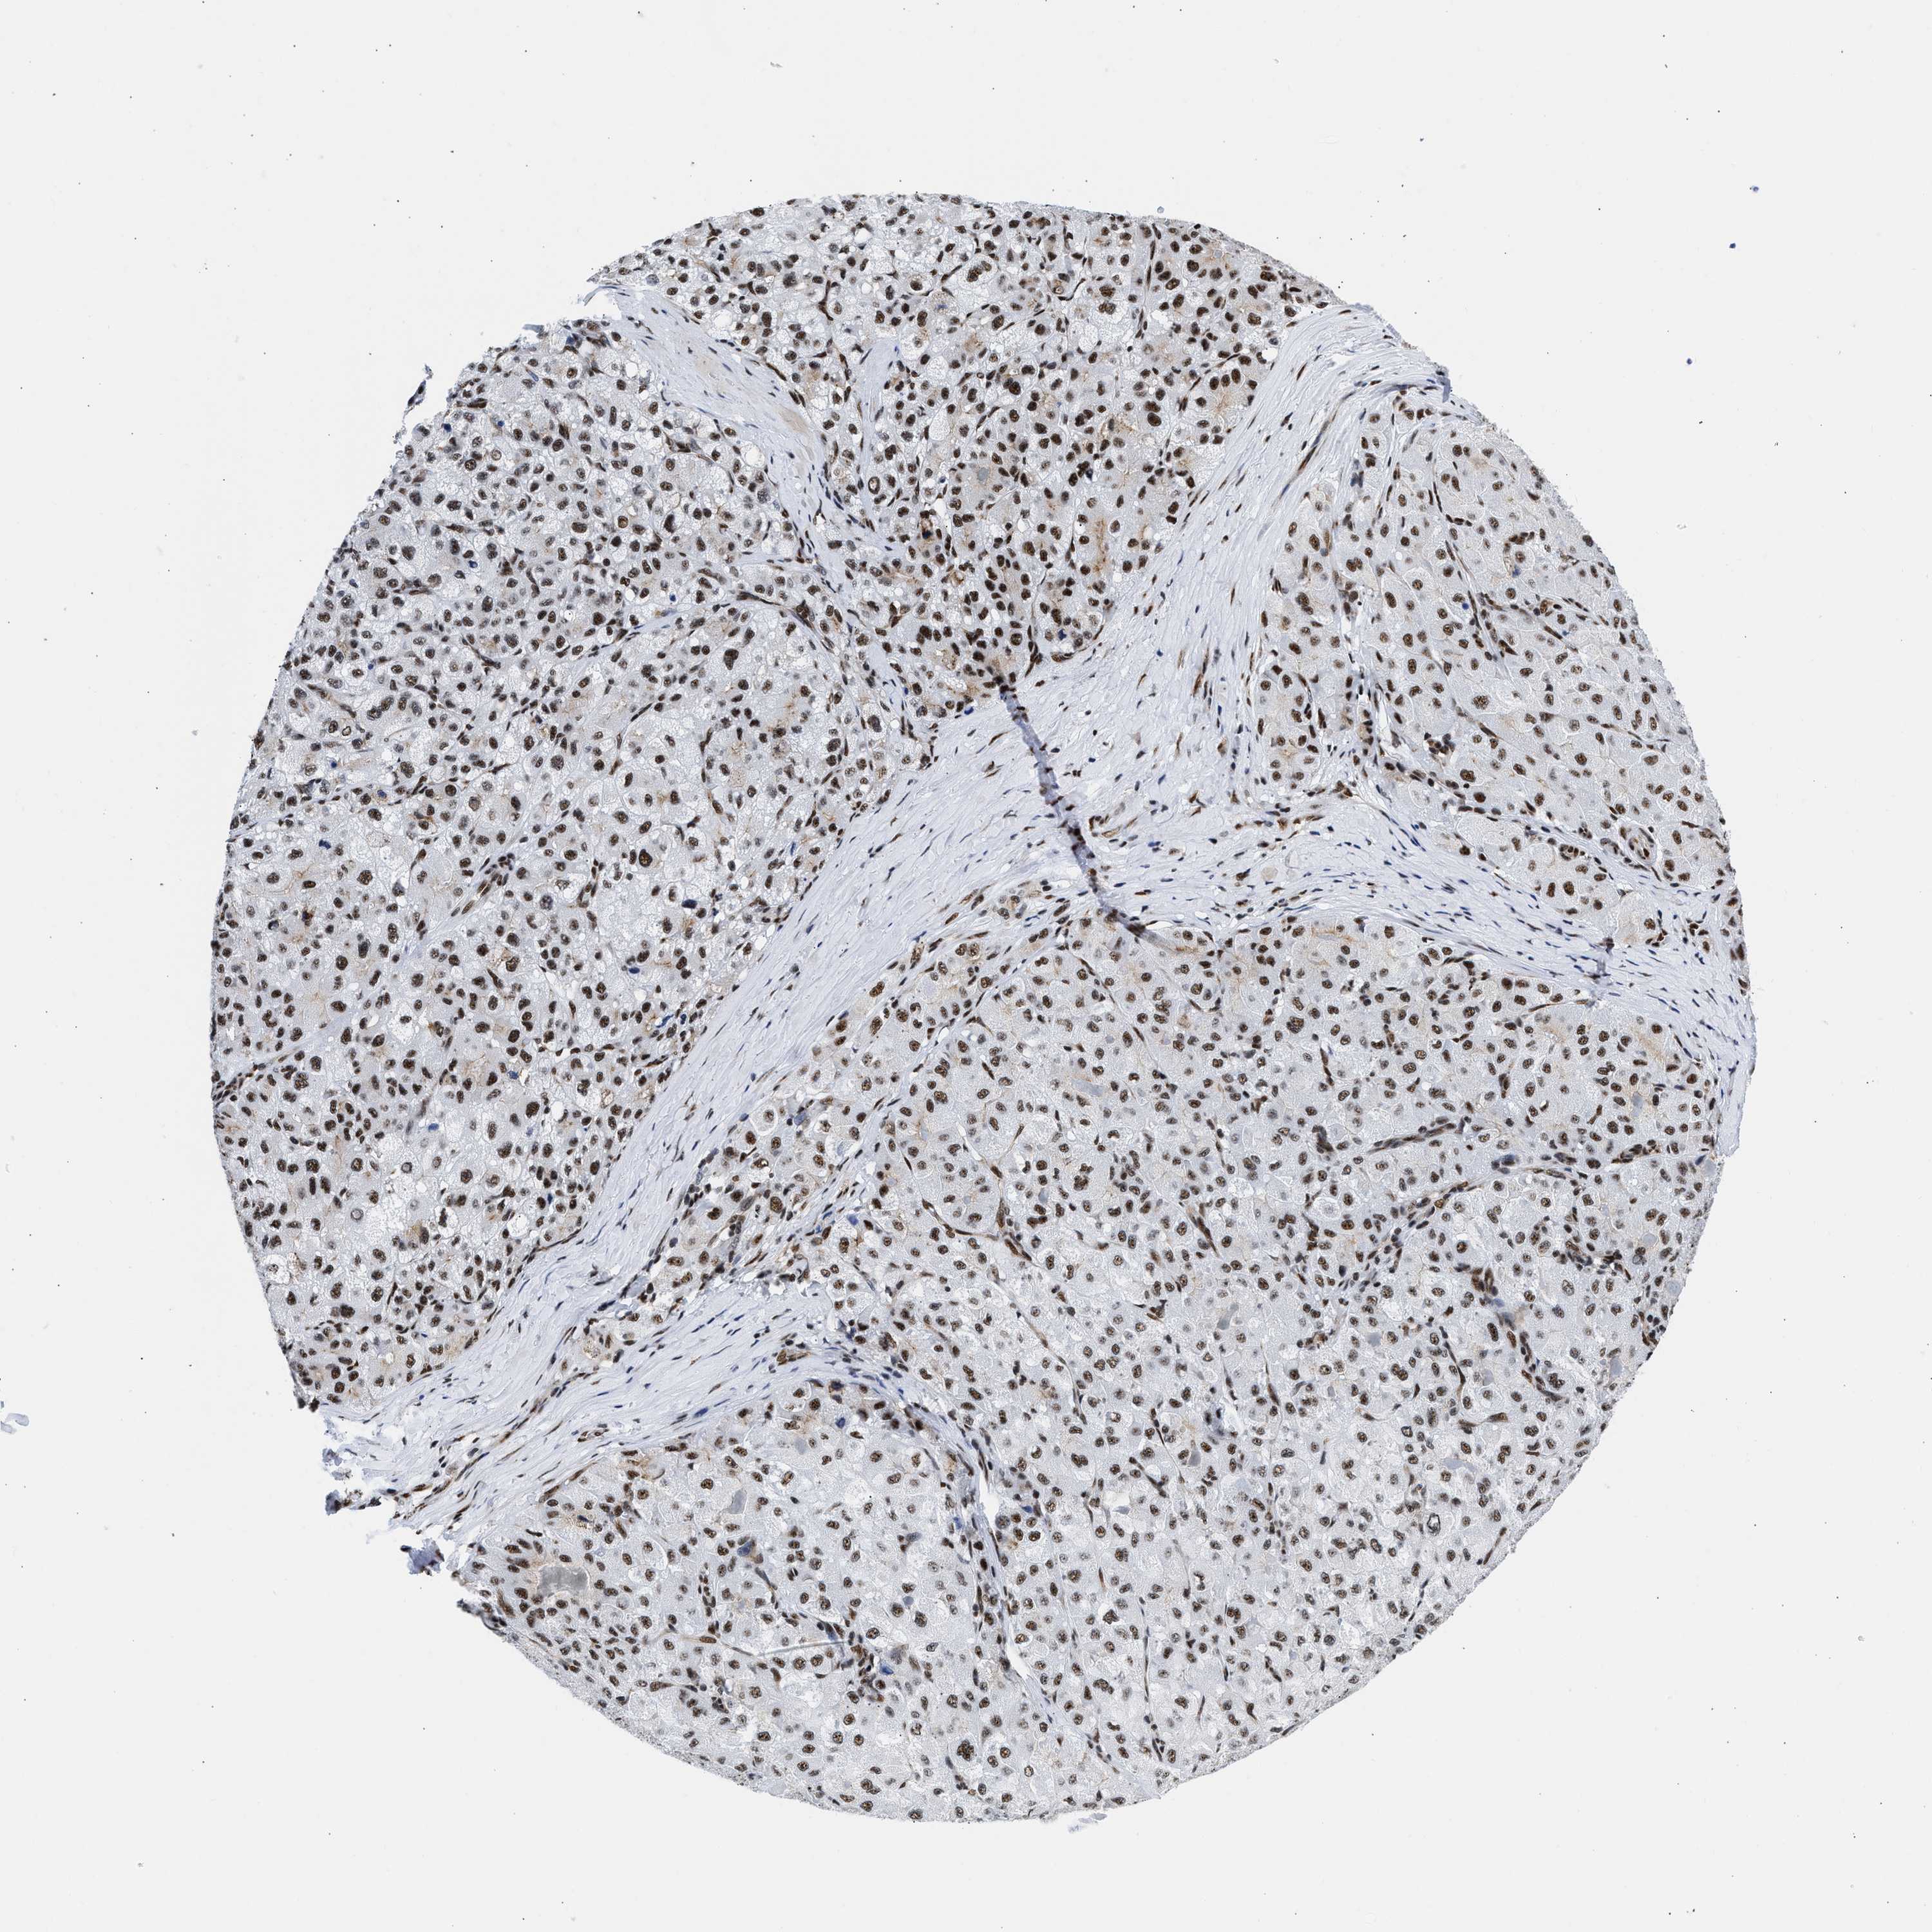

LIVER CANCER - Protein expressioni

A mouse-over function shows sample information and annotation data. Click on an image to view it in a full screen mode. Samples can be filtered based on level of antibody staining by selecting one or several of the following categories: high, medium, low and not detected. The assay and annotation is described here.

Note that samples used for immunohistochemistry by the Human Protein Atlas do not correspond to samples in the TCGA dataset.

Antibody stainingi

Antibody staining in the annotated cell types in the current human tissue is reported as not detected, low, medium, or high, based on conventional immunohistochemistry profiling in selected tissues. This score is based on the combination of the staining intensity and fraction of stained cells.

Each image is clickable and will lead to virtual microscopy that enables deeper exploration of all samples and also displays staining intensity scores, fraction scores and subcellular localization as well as patient and tissue information for each sample.

Antibody HPA018403

Staining

High

Medium

Low

Not detected

Intensity

Strong

Moderate

Weak

Negative

Quantity

>75%

75%-25%

<25%

None

Location

Nuclear

Cytoplasmic/membranous

Cytoplasmic/membranous,nuclear

Cholangiocarcinoma

Carcinoma, Hepatocellular, NOS